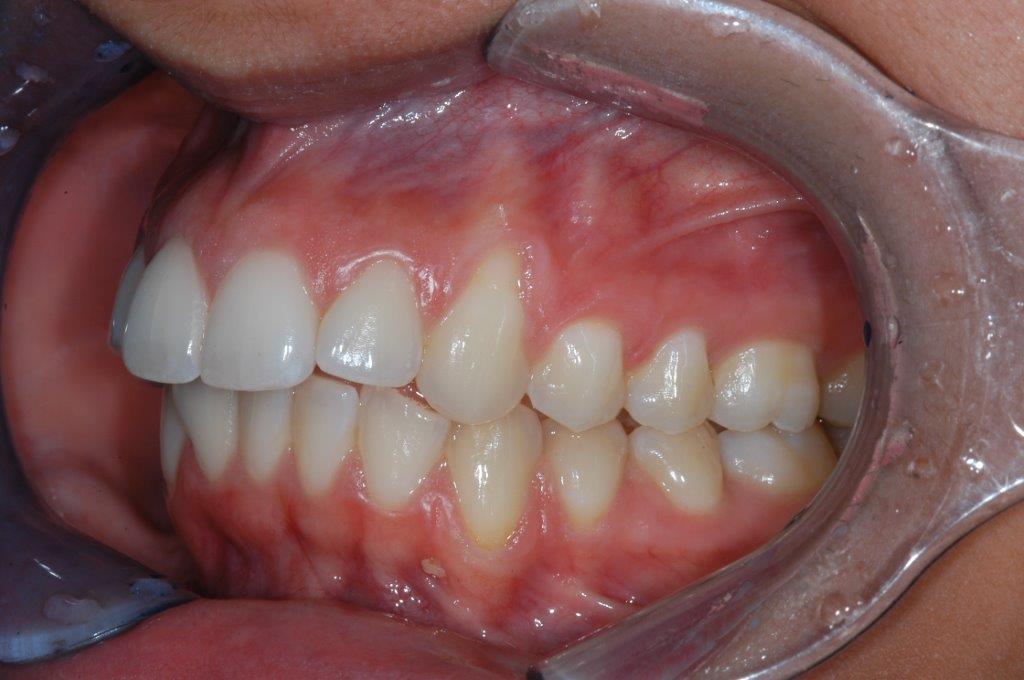

This young patient was self-conscious about the appearance of her short teeth and gummy smile. Through crown lengthening and tooth whitening procedures, we were able to create a beautiful, more mature smile.